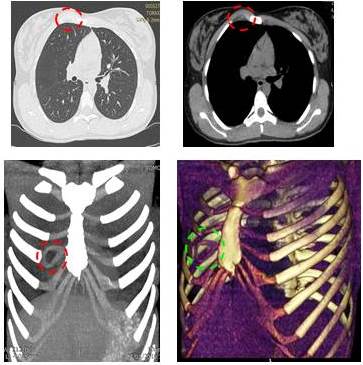

En la exploración imageneológica en la radiografía simple de tórax posteroanterior, no se evidencia imagen compatible a lesiónes ni trazos de fractura (Figura 1). En la tomografía computada de tórax con reconstrucción en 3D de pared torácica ósea-cartilaginosa, no se evidencia fractura, pero se identifica tumor cartilaginoso que ocupa todo el cuerpo del cuarto cartílago costal derecho de la unión articular condro-esterno-costal, abombando y adelgazando las corticales, con lesión lítica de coloración más oscura, rodeada de un halo de hiperdensidad (esclerosis) que lo delimita. Con un patrón condral muy bien delimitado (se ve la lesión rodeada por un halo) con alta sospecha de un tumor de origen condral compatible con lesión neoplásica benigna. Resto del plano óseo y blando sin evidencia de lesiones (Figura 2 A y B).

Debido a los hallazgo de imágenes, se procede a realizar toracotomía anterior derecha por planos a nivel del 4to y 5to espacio intercostal con resección quirúrgica del cuarto cartílago costal con su desarticulación esterno-condro-costal (Figura 3).